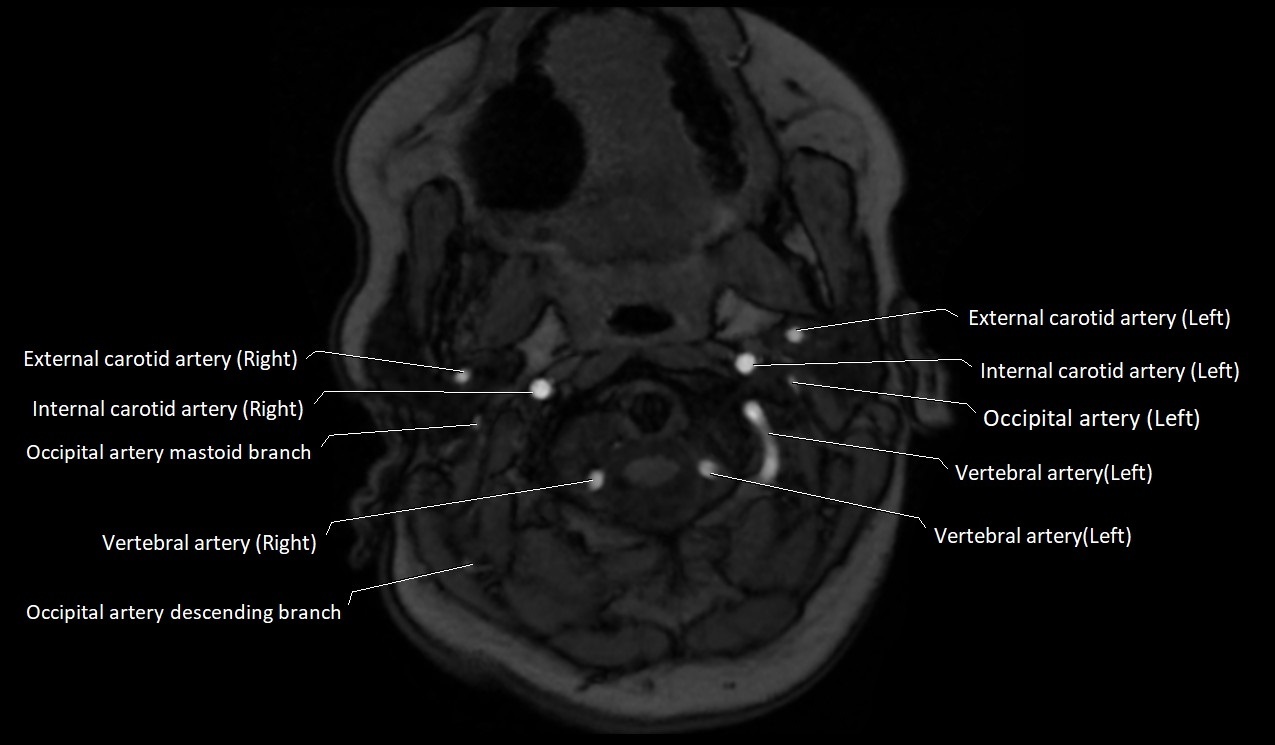

MRI Appearance:

• T1-Weighted Images:

• Appears as a tubular, hypointense (dark) structure relative to muscle

• May show flow void if the blood flow is fast

• T2-Weighted Images:

• Typically hypointense or isointense to muscle, but can be hyperintense if slow flow or stasis is present

MRI images